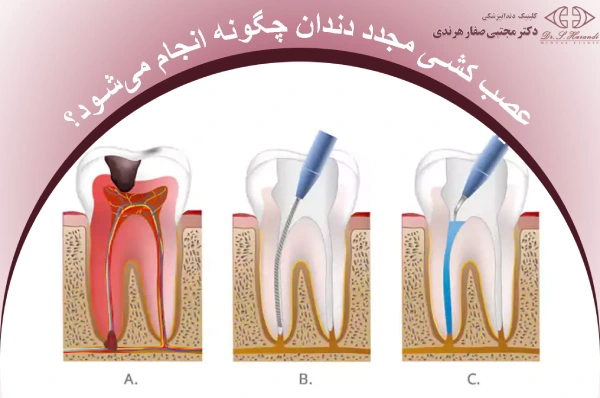

عصب کشی مجدد دندان چگونه انجام میشود؟

در این روش، دندانپزشک ابتدا دندان را بیحس میکند و مواد پرکنندهی قدیمی را از داخل ریشه خارج میسازد تا مسیرها بهطور کامل تمیز و قابل دسترسی شوند. سپس کانالهای ریشه با ابزارهای ظریف و مواد ضدعفونی شسته و پاکسازی میشوند تا هرگونه باقیماندهی میکروب یا بافت آلوده از بین برود.

پس از آمادهسازی، کانالها با مواد مخصوص پر میشوند تا از ورود دوبارهی باکتری جلوگیری شود. در نهایت، سطح دندان ترمیم و پوشش داده میشود تا ساختار آن مقاومتر شده و عملکرد طبیعی خود را بازیابد.